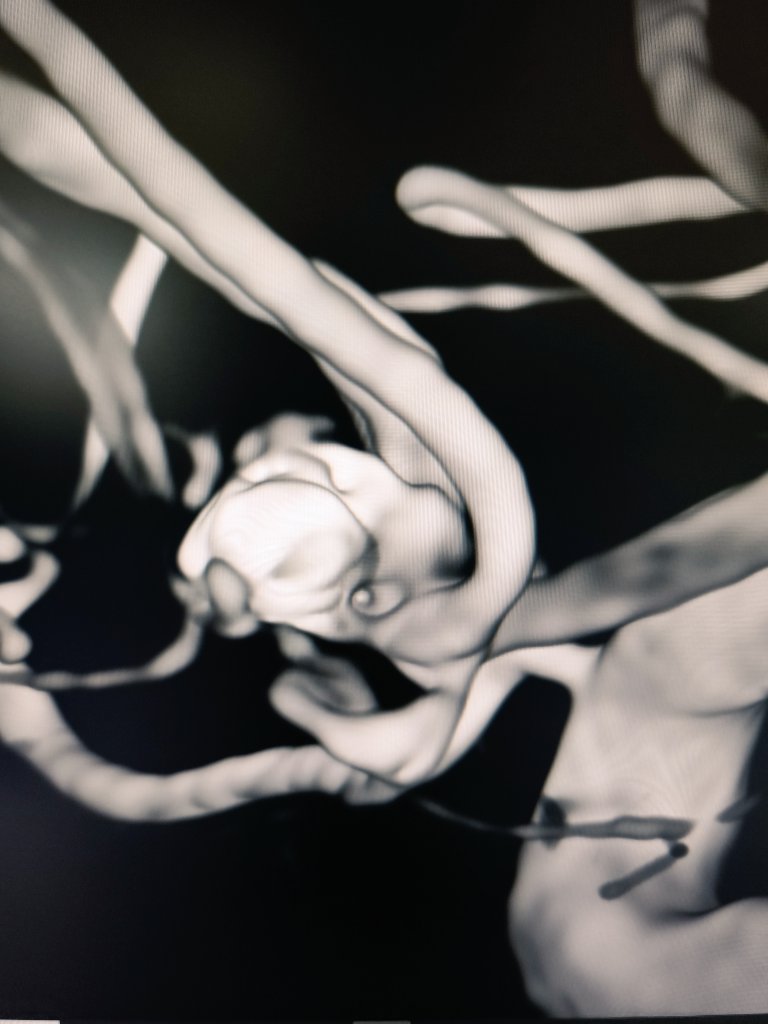

Mycotic (infectious) cerebral aneurysm (CA) resulting from infection of the arterial wall secondary to bacterial endocarditis. Represent < 5% of all CA

We treated it with endovascular glue (NBCA) embolization, complete closure, no deficit

@Sremollo

@IsaRCaamano

Rosa García Sort